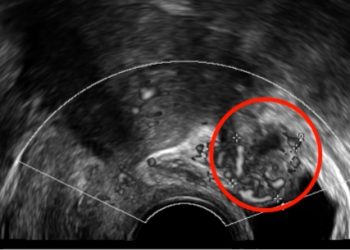

Cari soci, questo mese un nuovo video "How to do", sulla diagnosi ecografia di aborto nel primo trimestre. Grazie a...